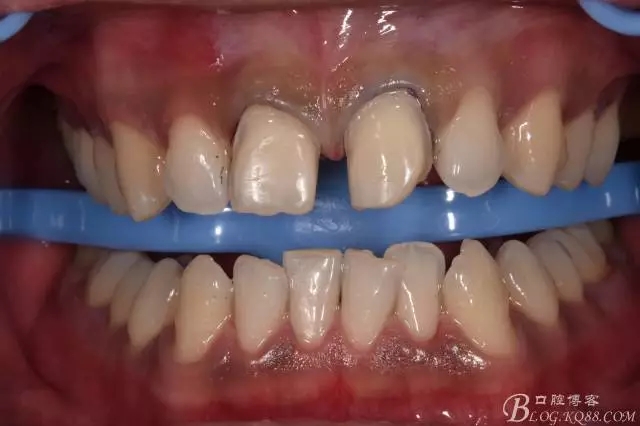

幾天后到貨

義獲嘉套裝,試色后,酸蝕后粘結(jié)。